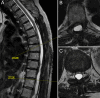

Observations: Here, the authors describe a 57-year-old female with a thoracic intradural arachnoid cyst that recurred despite extensive and initially successful fenestration. Given the failure of fenestration, the authors instead attempted to place a cystoperitoneal shunt. Given how extensive her laminectomy was, the authors elected to perform the procedure under ultrasonic guidance to avoid the large incision required for open shunt placement. The procedure was successful, with gradual improvement in the size of the arachnoid cyst as well as symptomatic improvement.